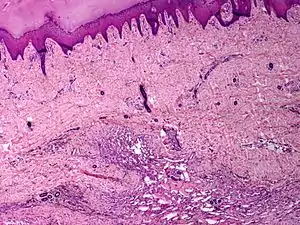

Angiomatosis is a non-neoplastic condition[1] characterised by nests of proliferating capillaries arranged in a lobular pattern, displacing adjacent muscle and fat.[2] It consists of many angiomas.[3]

| Skin angiomatosis | |

These tend to be cavernous hemangiomas, which are sharply defined, sponge-like tumors composed of large, dilated, cavernous vascular spaces.

It is a vascular malformation wherein blood vessels proliferate along with accompanying mature fat and fibrous tissue, lymphatics and sometimes nerves.[2] They may involve skin, subcutaneous tissue, skeletal muscle and occasionally bone.[2]